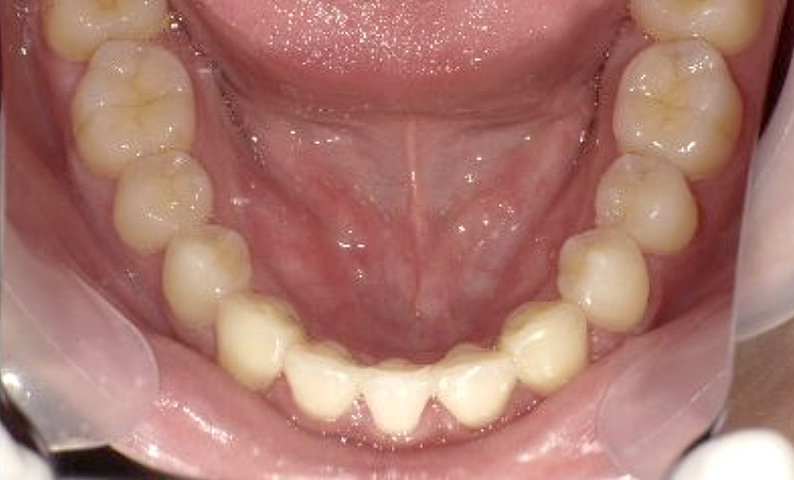

症例_001 下顎だけの部分矯正

治療期間:6ヶ月金額:27万円+税女性前歯のガタガタ下の前歯だけ

| Before | After |

|---|---|

|